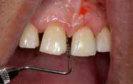

Applikation des OXYSAFE Gels in situ Patientensituation 3 Wochen nach Beginn der Sauerstofftherapie mittels OXYSAFE

Anwendung von OXYSAFE®

Beispielhaft nun die Anwendug von OXYSAFE am Frontzahn

11. Die Sondierungstiefe beträgt sowohl mesial als auch distal 7 mm an Zahn 11 und es liegt eine Blutung vor. Es liegt ein vertikaler Knochenverlust vor.

Reinigen der Zahnfleischtasche Erste direkte Applikation des Gels in die Zahnfleischtasche Fortsetzung der Behandlung durch den Patienten zuhause 3 täglich 10 ml Zweite Applikation des Gels in die Zahnfleischtasche und dort belassen >> Keine Antibiotika >> Kein CHX >> Über 20 Jahre klinische Erfahrung ca. 2,74 € pro Zahnfleischtasche Aktion Jetzt gratis testen!*